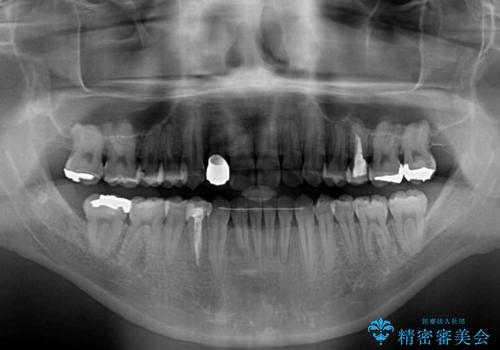

- 前歯のデコボコとクロスバイトを気にして来院された患者様です。

下顎の歯列弓に対して上顎歯列弓がやや小さく、側方の歯を中心にクロスバイトが見受けられました。

クロスバイトの改善は、インビザラインの場合歯髄壊死のリスクや咬み合わせが改善しきらないリスクがあるため、ワイヤー矯正をお勧めすることが多いですが、患者様の希望によりインビザラインにて矯正治療を行うこととしました。

後方に隠れていた上顎前歯は矮小歯であるため、矯正治療の途中でオールセラミッククラウンを装着し、左右対称の大きさでの仕上がりを目指すこととしました。

奥歯の咬み合わせは接触が少なく物足りないように見えますが、患者様としては十分に咬むことができるとのことでした。